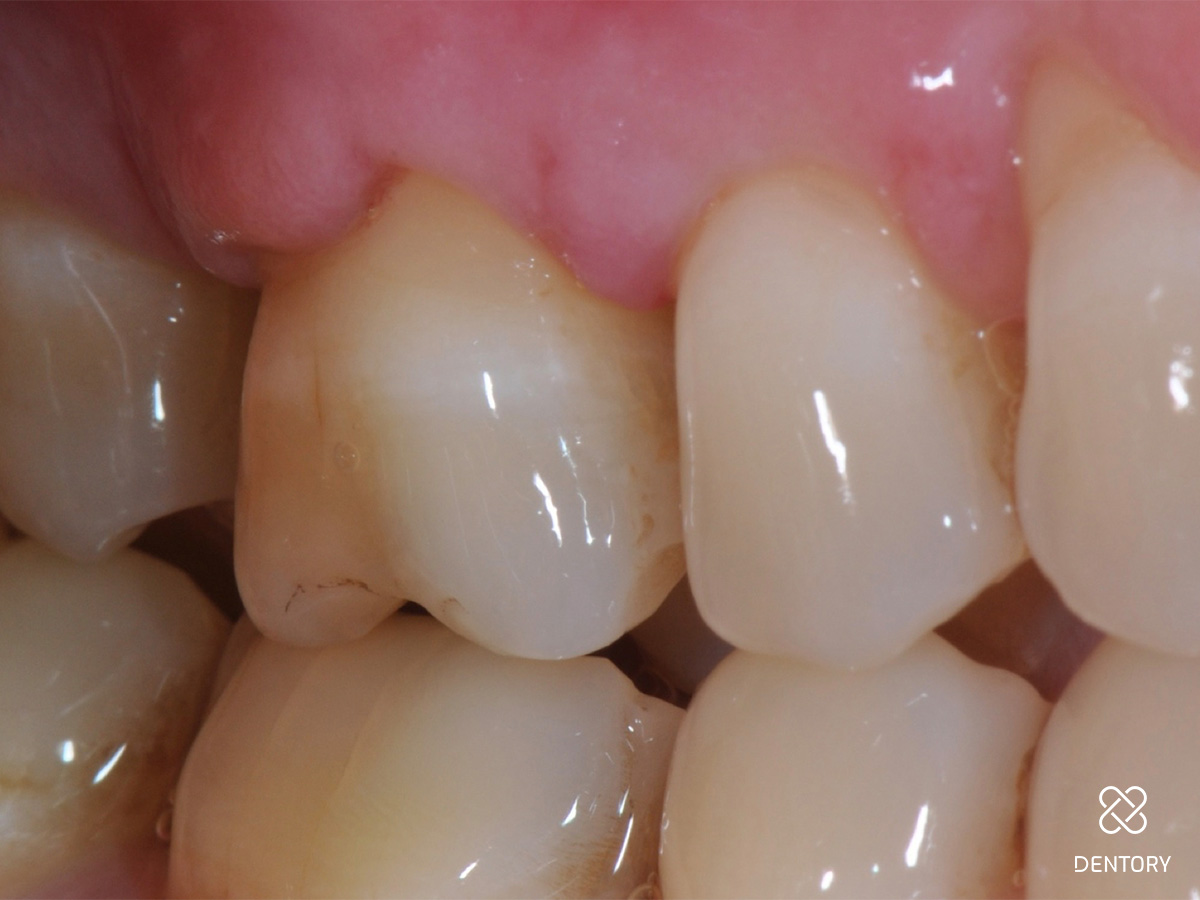

Abbildung 1

Ausgangssituation: Frontalansicht.